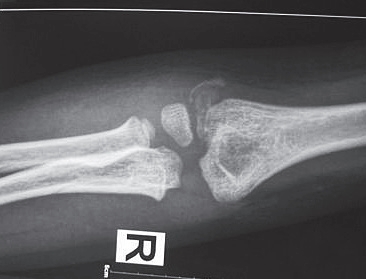

图7-2 肱骨髁骨折术后X线片

4.手术治疗 肱骨髁骨折切开复位内固定术(图7-2)。